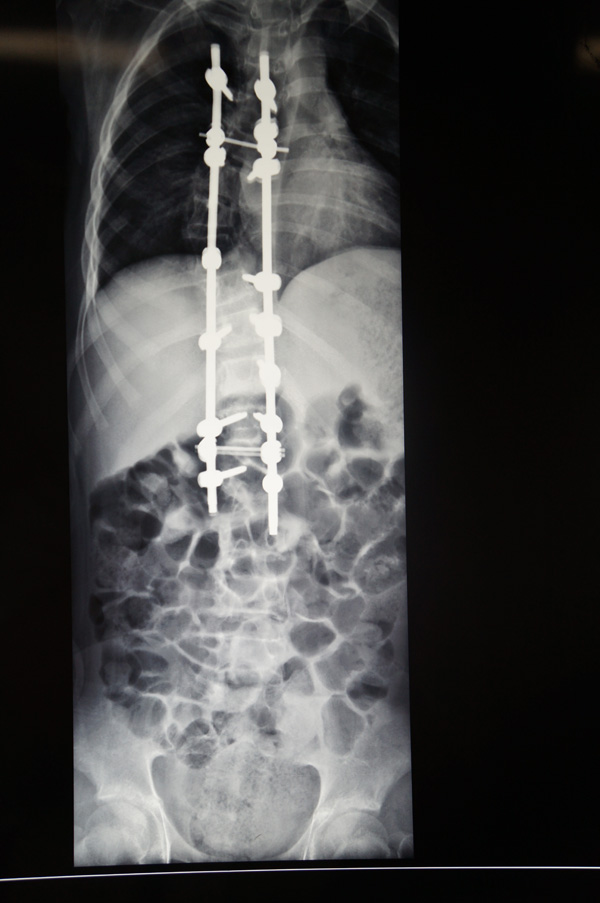

现在,经过手术后的小松脊柱外观基本恢复了正常,他感到背部没有明显的疼痛,且背部的手术伤口也愈合良好,没有发热头晕头痛和恶心呕吐等不适症状,饮食睡眠都很好,四肢感觉、运动、肌力正常。

小松术后的X光片